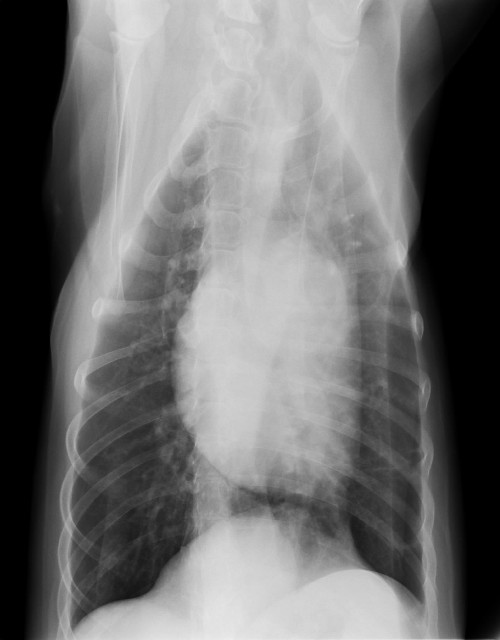

●レントゲンも3枚(胸・腰)撮りました。

うちの獣医さん、この秋にレントゲンをデジタル化したの。

だから、画像をCDに落としてもらえるようになったんだよヽ(*'0'*)ツ

キレイだからべべちゃんの“ヌード”3枚見てね。

診断としては、内臓関係は肺以外みんなOK(^^)v

肺は、べべは6歳半でうちに帰ってきた時にすでにフィラリアに罹っていて、肺に成虫が達していて、それを治療した残骸がある?し、フィラリアの影響か?肺のあちこちが石灰化してるの(前から)

背骨は変形性脊椎症であちこちブリッジにはなっているけど、これからも関節サプリ/アースリスージゴールドやマッサージやレーザーで手当てしてあげながら上手く着きあっていけば大丈夫♪